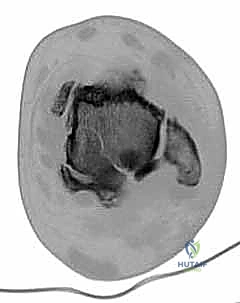

CT scan shows fatigue fractures through avascular talar body ( TECH FIG 7D,E ).

TECH FIG 7 • A. Patellar tendon bearing brace. B, C. Preoperative radiographs of patient with talar body avascular necrosis. D, E. CT scan of same patient in A . Note fatigue fractures in the talar body.